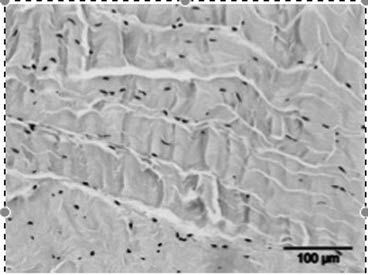

• Het stimuleren van de collageenproductie en het afvoeren van beschadigd collageen, wat resulteert in een verhoogde matrix-turnover.

Een tweede hypothese is dat ESWT een positief effect heeft op weefselregeneratie door:

• De toename van neovascularisatie in de pees-bot overgang.

•  Het opwekken van groeifactoren zoals vasculo-endothelial growth factor (vegf).

• Het beïnvloeden van stamcelmigratie en -proliferatie via mechanotransductie.

• De stijging in de celpermeabiliteit. De stimulatie van de celdeling.